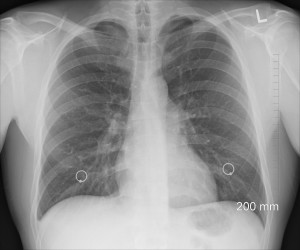

Lungenkrebs: ASOs als neue vielversprechende Alternative (Foto: pixabay.com, oracast) |